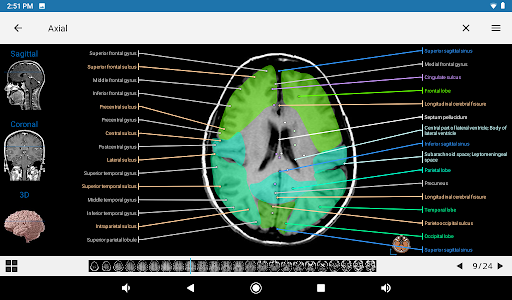

e-Anatomy tiene más de 26 000 imágenes que contienen series de imágenes en vistas axiales, coronales y sagitales, así como radiografías, angiografías, imágenes de disección, gráficos anatómicos e ilustraciones. Todas las imágenes médicas fueron etiquetadas cuidadosamente, más de 967 000 etiquetas disponibles en 12 idiomas, incluida la Terminologia Anatomica latina.

- Toque las etiquetas para mostrar las estructuras anatómicas

- La vista anatómica ahora muestra más etiquetas